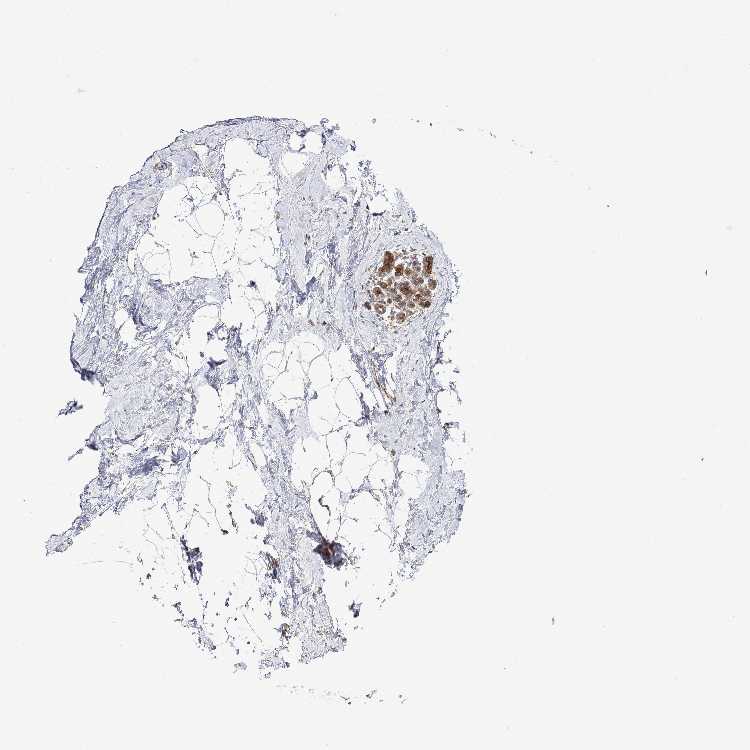

BREAST - Antibody stainingi

Antibody staining in the annotated cell types in the current human tissue is reported as not detected, low, medium, or high, based on conventional immunohistochemistry profiling in selected tissues. This score is based on the combination of the staining intensity and fraction of stained cells.

Each image is clickable and will lead to virtual microscopy that enables deeper exploration of all samples and also displays staining intensity scores, fraction scores and subcellular localization as well as patient and tissue information for each sample.

Antibody HPA049854Antibody HPA056520

Adipocytes Not detectedNot detected

Glandular cells MediumMedium

Myoepithelial cells MediumLow